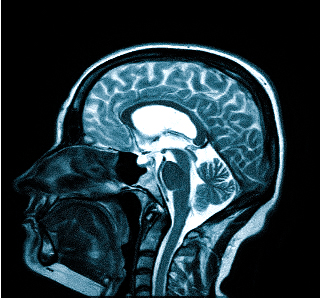

- МРТ (магнитно-резонансная томография) — процедура, которая предоставляет полное представление о состоянии исследуемой области и о наличии заболеваний. Снимки получаются благодаря воздействию магнитного поля на организм.

Для процедуры пациент ложится на стол-транспортер, который заезжает в томограф — сканирующее устройство. На время обследования пациент находится в трубе и должен оставаться неподвижным для получения четкого изображения. Процедура занимает от 15 минут.

Особой подготовки не требуется, но необходимо предупредить врача о наличии клаустрофобии, так как это может быть противопоказанием. Если во время МРТ вы почувствуете недомогание, сообщите об этом специалисту, проводящему исследование МРТ головы.